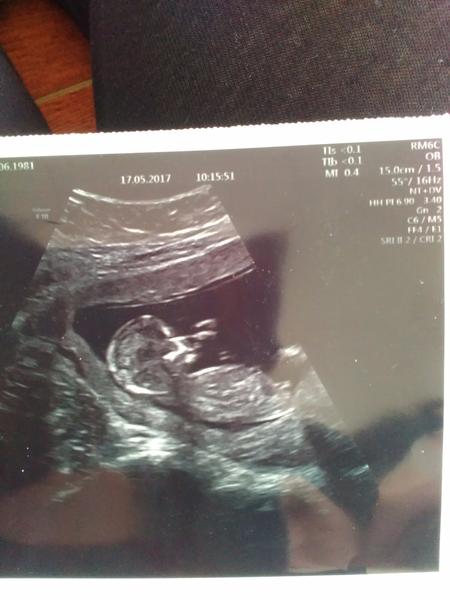

Je to holčička nebo chlapeček? Foto ultrazvuku

Jestli jsem se dobre zorientovala, pripadne mi to na holcicku, nevim. A dr rekla co?

Nejsem si úplně jistá, jestli je pohlaví na té fotce vidět právě. Ale je to chlapeček 🙂

@alhamdulillah pohlavní hrbolek bohužel není dobře vidět 😔